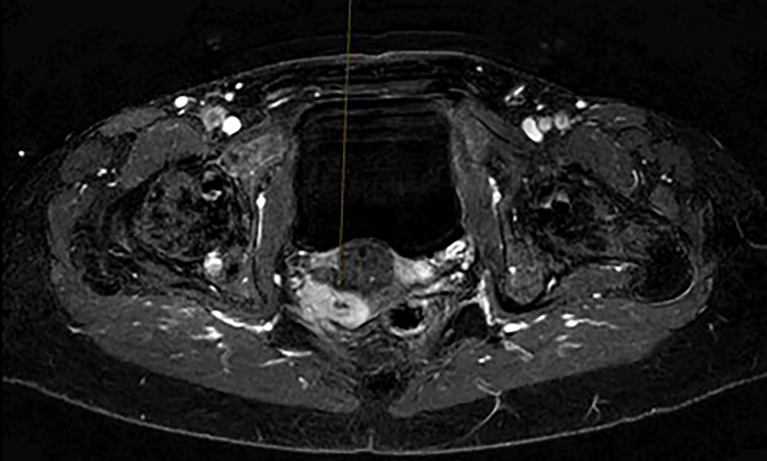

一名49岁患者被诊断出患有4cm的阴道透明细胞腺癌(VAC),肿瘤浸润骨盆侧壁(图1、2)。初步诊断时,在计算机断层扫描(CT)中检测到多发性肺转移瘤,大小可达5 mm。由于转移灶体积小,CT引导下穿刺肺转移灶似乎不可行。原发肿瘤的免疫组化显示激素受体阴性,p16表达阴性,Ki-67高达70%。由于局部晚期、无法手术的VAC伴右腿转移性疼痛,使用卡铂AUC5/紫杉醇80 mg/m²和贝伐单抗15 mg/kg q3w进行全身治疗。临床和图像形态学肿瘤消退。在完成六个周期的化疗后,继续贝伐单抗15mg/kg维持治疗。临床检查和影像学检查显示,单用贝伐单抗15 mg/kg四个周期后,局部和肺部疾病进展。重复肿瘤活检免疫组织化学显示所有错配修复蛋白稳定,PD-L1联合阳性评分(CPS)为2,ERBB2表达。

图1. 骨盆的初始磁共振成像扫描